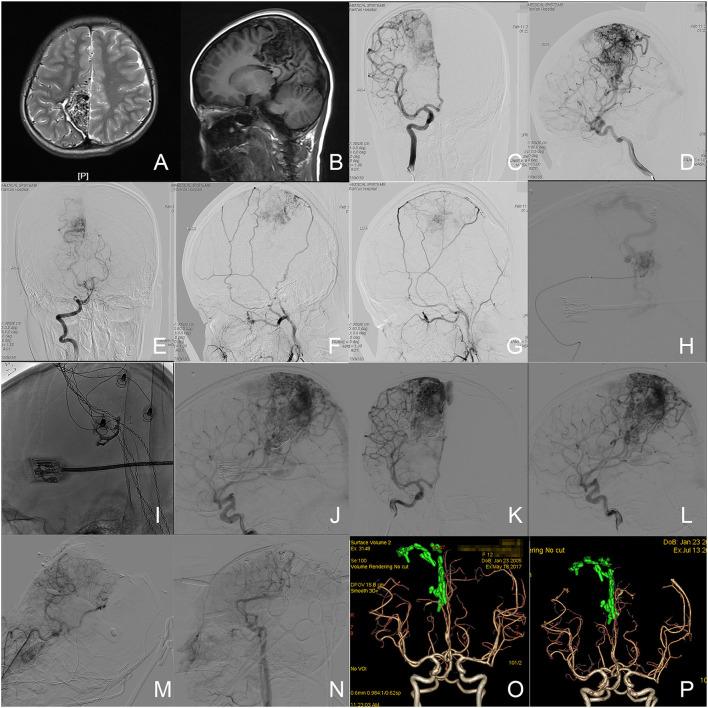

It remains a challenge in surgical treatments of brain arteriovenous malformations (AVMs) in Spetzler-Martin Grade (SMG) IV and V to achieve both optimal neurological outcomes and complete obliteration. The authors reported a series of patients with AVMs in SMG IV and V who underwent a surgical paradigm of endovascular embolization and simultaneous microsurgical resection based on the one-staged hybrid operation. Participants in the multicenter prospective clinical trial (NCT03774017) between January 2016 and December 2019 were enrolled. Patients who received endovascular embolization plus microsurgical resection (EE+MRS) and those who received intraoperative digital subtraction angiography plus microsurgical resection (iDSA+MRS) were divided into two groups. Information on clinical features, operative details, and clinical outcomes were extracted from the database. Deterioration of neurological deficits (DNDs) was defined as the primary outcome, which represented neurological outcomes. The time of microsurgical operation and blood loss were defined as the secondary outcomes representing microsurgical risks and difficulties. Outcomes and technical details were compared between groups. Thirty-eight cases (male: female = 23:15) were enrolled, with 24 cases in the EE+MRS group and 14 in the iDSA+MRS group. Five cases (13.2%) were in SMG V and 33 cases (86.8%) were in SMG IV. Fourteen cases (36.8%) underwent the paradigm of microsurgical resection plus intraoperative DSA. Twenty-four cases (63.2%, = 24) underwent the paradigm of endovascular embolization plus simultaneous microsurgical resection. Degradations of SMG were achieved in 15 cases. Of the cases, two cases got the residual nidus detected via intraoperative DSA and resected. Deterioration of neurological deficits occurred in 23.7% of cases ( = 9) when discharged, and in 13.5, 13.5, 8.1% of cases at the follow-ups of 3, 6, and 12 months, respectively, without significant difference between groups ( > 0.05). Intracranial hemorrhagic complications were reported in three cases (7.9%) of the EE+MRS group only. The embolization did not significantly affect the surgical time and intraoperative blood loss. The subtotal embolization or the degradation of size by 2 points resulted in no DNDs. The paradigms based on the one-staged hybrid operation were practical and effective in treating high-grade AVMs. Appropriate intraoperative embolization could help decrease operative risks and difficulties and improve neurological outcomes.

在Spetzler-Martin分级(SMG)IV级和V级脑动静脉畸形(AVM)的外科治疗中,实现最佳神经学预后和完全闭塞仍然是一项挑战。作者报告了一系列SMG IV级和V级AVM患者,他们接受了基于一期杂交手术的血管内栓塞联合显微手术切除的手术模式。纳入了2016年1月至2019年12月期间多中心前瞻性临床试验(NCT03774017)的参与者。接受血管内栓塞加显微手术切除(EE+MRS)的患者和接受术中数字减影血管造影加显微手术切除(iDSA+MRS)的患者被分为两组。从数据库中提取临床特征、手术细节和临床结果的信息。神经功能缺损恶化(DND)被定义为主要结局,代表神经学预后。显微手术时间和失血量被定义为代表显微手术风险和难度的次要结局。比较两组的结局和技术细节。共纳入38例患者(男∶女=23∶15),EE+MRS组24例,iDSA+MRS组14例。5例(13.2%)为SMG V级,33例(86.8%)为SMG IV级。14例(36.8%)患者接受了显微手术切除加术中DSA的模式。24例(63.2%,n=24)患者接受了血管内栓塞联合显微手术切除的模式。15例患者实现了SMG降级。其中,2例患者通过术中DSA检测到残留病灶并进行了切除。出院时23.7%(n=9)的患者出现神经功能缺损恶化,在术后3、6和12个月的随访中,分别有13.5%、13.5%和8.1%的患者出现神经功能缺损恶化,两组之间无显著差异(P>0.05)。仅EE+MRS组有3例(7.9%)患者报告了颅内出血并发症。栓塞对手术时间和术中失血量无显著影响。次全栓塞或体积缩小2级未导致DND。基于一期杂交手术的模式在治疗高级别AVM方面切实有效。适当的术中栓塞有助于降低手术风险和难度,并改善神经学预后。